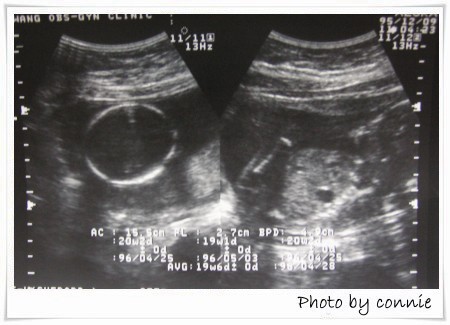

第四次產檢:

日期:95年12月09日

週數:19周+

血壓:135/92

尿蛋白,血糖:正常